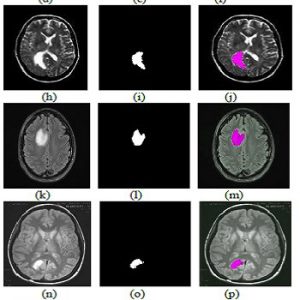

این شبیه سازی با استفاده از نرم افزار متلب (MATLAB) انجام شده و در ادامه نیز تعدادی از نتایج خروجی آن قرار داده شده است:

تومور، تورم قسمتی از بدن، معمولاً بدون هرگونه التهابی است که بخاطر رشد غیرعادی سلول ها در آن مکان از بدن رخ می دهد. تشخیص تومور مغزی در مراحل اولیه دشوار است. این تومور بوسیله تصویربرداری تشدید مغناطیسی (MRI) تشخیص داده می شود، و براساس آن، تومورها به درجات شدت مختلف، تقسیم می شوند. این پروژه، روش جدیدی برای آشکار سازی و استخراج تومور از تصاویر کلی، ارائه می دهد. این پروژه، طرحی برای استخراج تومور از MRI براساس خوشه بندی FCM (C-means فازی) مبتنی بر GA (الگوریتم ژنتیک) و عملیات های ریخت شناسی، پیشنهاد می دهد. شبیه سازی های کامپیوتری الگوریتم ما، بهبود قابل ملاحظه نسبت به روش های موجود دیگر را نشان می دهند. نتایج شبیه سازی نیز حاکی از بازده خوب روش پیشنهادی است.